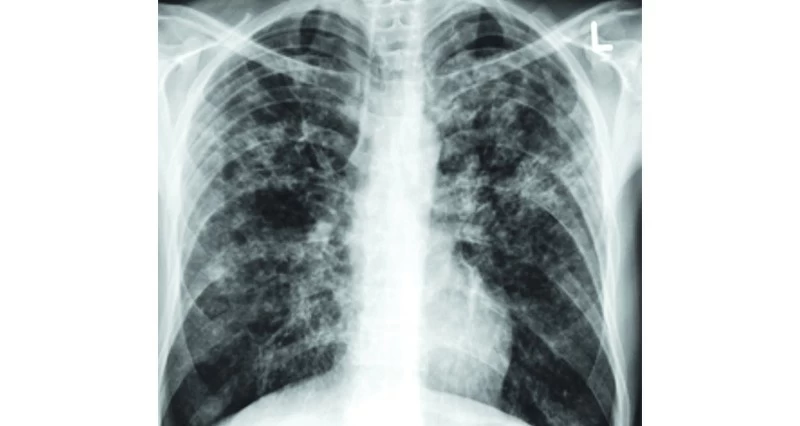

الصحة تعزز جهود مكافحة مرض السل وتواصل الحفاظ على معدلات إصابة منخفضة

مسقط ـ العُمانية: تواصل سلطنة عُمان جهودها الحثيثة في مكافحة مرض السل، الذي يُعدّ أحد أبرز التحديات الصحية على مستوى العالم، كونه من الأمراض المعدية الرئيسة المسببة للوفاة عالميًا، وذلك عبر تنفيذ برامج متكاملة تستهدف الوقاية والكشف المبكر والعلاج وتعزيز الوعي المجتمعي.

وقد أسهمت هذه الجهود في الحفاظ على معدلات إصابة منخفضة، حيث تُصنَّف سلطنة عُمان وفق المعايير الدولية ضمن الدول منخفضة الإصابة.

وبلغ معدل الإصابة في عام 2025 نحو 8.5 حالات لكل 100 ألف نسمة، مع متوسط تسجيل يقارب 300 حالة سنويًا، معظمها من الوافدين القادمين من الدول عالية الإصابة، نتيجة لتحوّل الجرثومة الكامنة التي سبق الإصابة بها في بلد المغادرة إلى الشكل النشط بسبب عدة عوامل، منها التغيّر في البيئة، والتغذية، والمناعة، وغيرها.